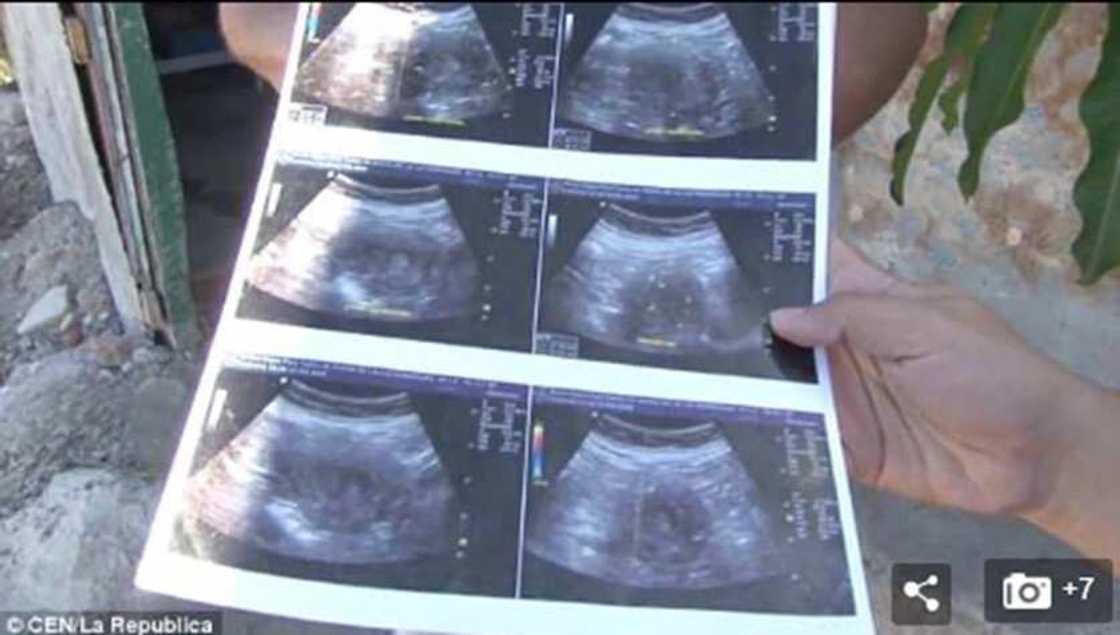

A wani labari mai cike da al'ajabi tare da tabbatar da buwayar Allah, mun samu cewa an samu wata mata mai suna Maria de la Luz a kasar Mexico mai shekaru 70 a duniya da ta ce tana dauke da ciki wata shidda.

Da take zantawa da majiyar mu a garin nata, tsohuwar da yanzu haka take jiran haihuwar dan ta na takwas ta ce ta tabbatar da shigar cikin na ta ne biyo bayan sakamakon hoton cikin da ta yi aka kuma fada mata cewa mace ce za ta haifa.

Yanzu dai kamar yadda muka samu cewa tuni sun kammala shire-shire da likitan ta wanda ya fada mata cewa za ayi mata tiyata a ciro diyar idan lokacin haihuwar ta yayi.